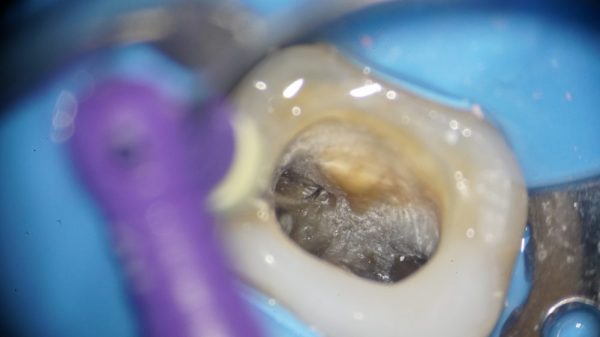

これは上の奥歯の治療途中の写真です。

これは上の奥歯の治療途中の写真です。

数年前に他院で根の治療を行っており、最近歯茎が腫れてきて当院に来院された患者さんです。

根管には古い充填材が入っています。

黄色い丸が根管です。これは上の前から6番目の奥歯であれば大体同じ位置に根管があります。

黄色い丸が根管です。これは上の前から6番目の奥歯であれば大体同じ位置に根管があります。

そして、以前の治療もそこには充填材が入っており、治療をした痕跡がありました。

探してみると、この歯は4つ目の根管がありました。

探してみると、この歯は4つ目の根管がありました。

細いファイルが4つ目も根管に入っているのがわかります。

ここは全く手付かずで、内部が汚れており、膿が出てきました。